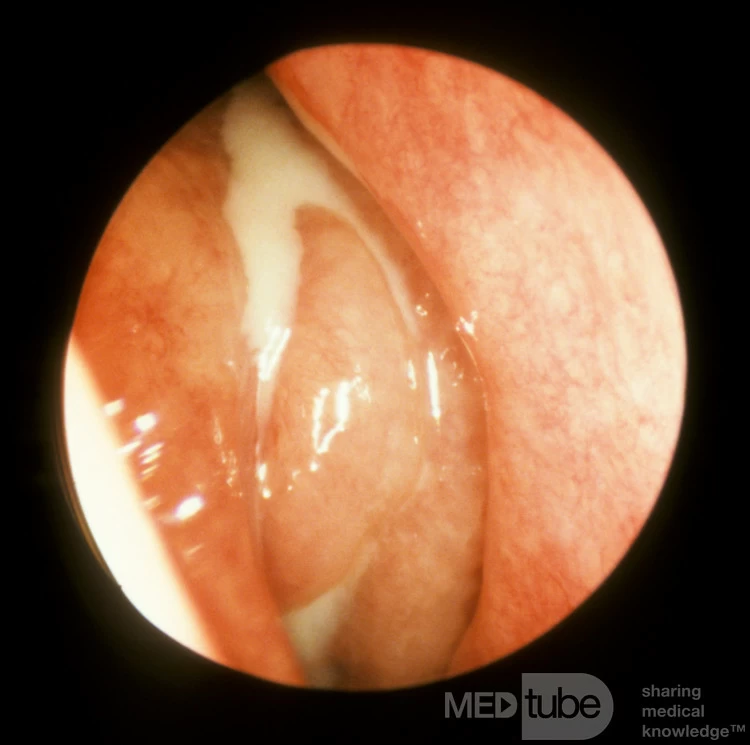

Đây là lỗ thông giữa bên phải của một bệnh nhân vẫn tiếp tục bị các đợt viêm xoang tái phát mặc dù đã được phẫu thuật mở thông dưới và cắt bỏ một phần cuốn mũi dưới. Chụp ảnh tại thời điểm xảy ra đợt cấp: có thể thấy polyp, mô hạt và mủ ở lỗ thông giữa. Lưu ý cách mủ di chuyển về phía sau trực tiếp qua lỗ thông của vòi nhĩ. Được cung cấp bởi Giáo sư Heinz Stammberger, Đại học Graz, Áo.